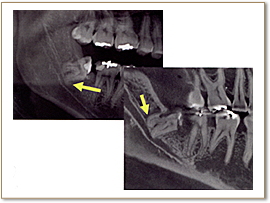

※左上図:インプラント埋入シュミレーション

右上図:インプラント埋入後確認

歯周病は、細菌感染による骨の破壊が起きる病気であるため、骨の破壊の程度などをよりリアルに見て判断することができます。また、骨の状態からおおよその歯の寿命を積算することも可能です。従って、非常に予知性の高い治療が行えます。

※右上図:歯周病により奥歯のさらに奥の骨が破壊されている

歯科用CTを親知らずの抜歯に利用することで、立体的に把握することができます。これにより、神経を引っ掛けてしまう可能性や、周囲の炎症の程度、病巣の有無や大きさ、位置なども判断・考慮して、治療を行うことができます。また埋伏歯などの位置なども精密に判断できるので、余分な切開や骨の切削などを避けることができます。

※下顎管(下顎に沿って通っている神経の束)と親知らずが密接している。気付かずに神経を傷つけてしまうと顎のマヒなどを起こすこともある